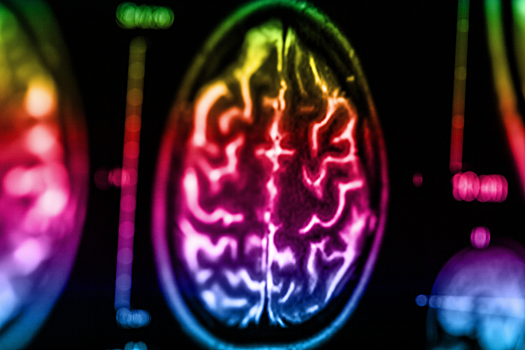

Еще в подростковом возрасте Саманта Тейлор из Лондона начала испытывать сильные головокружения, которые могли возникать даже во сне. И только несколько лет спустя, когда девушке исполнилось 18 лет, магнитно-резонансная томография выявила у нее маленькую опухоль, которая в последствие обернулась для Саманты большими проблемами. Обнаруженная опухоль оказалась доброкачественной , и врачи решили оставить все как есть и лишь каждые шесть месяцев наблюдать за ее ростом. Со временем, беспокоящие Саманту симптомы сошли на нет только лишь для того, похоже, чтобы через четыре года вернуться с удвоенной силой. Сильнейшие головокружения дополнили проблемы со зрением. МРТ показала, что опухоль разрослась до размера 2,2 см, и врачи приняли решение ее удалить. К сожалению, во время операции произошло несчастье, риск которого обычно составляет 5%. Из-за недостаточного поступления крови в мозг у Саманты случился инсульт мозжечка, в результате которого у девушки парализовало правую часть лица и временно пропало зрение. Врачи затрудняются сказать, насколько быстро Саманте удастся восстановиться. Одни люди приходят в себя в течение нескольких дней, другие - месяцев, а к кому-то после перенесенного инсульта чувствительность лица и вовсе не возвращается. К счастью, у Саманты со временем постепенно восстановилось зрение. Сейчас все силы девушки направлены на интенсивные занятия физиотерапией. Она заново учится таким элементарным казалось бы вещам, как пить с помощью трубочки, держать в руках стакан с водой, открывать ключом дверь, подниматься и спускаться с эскалатора и прочим навыкам повседневной жизни. Сегодня Саманта занимается просветительской деятельностью и даже завела свой блог и аккаунт в одной из социальных сетей, чтобы документировать свою жизнь и вдохновлять собственным примером других людей, страдающих от опухоли мозга. _Фото: Vostock-photo, Instagram _ Подписывайтесь на страницы Passion.ru в ВКонтакте, Одноклассниках, Facebook и Instagram!